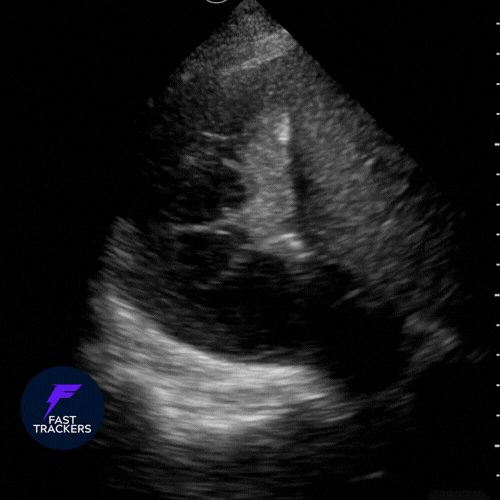

🫁 Consolidation (syndrome alvéolaire)

Substitution de l’air alvéolaire par du liquide ou de l’inflammation : le parenchyme prend un aspect tissulaire (« hépatiforme »).

- Aspect tissulaire : zone échogène, granuleuse, proche de l’aspect du foie.

- Bronchogrammes aériques : air circulant dans les bronches visibles au sein d’une condensation.

- Bronchogrammes dynamiques : signal Doppler couleur avec la respiration → pneumonie (voies aériennes perméables).

- Bronchogrammes statiques : immobiles → atélectasie (obstruction bronchique).

- Poumon “déchiqueté” : limite irrégulière entre le poumon aéré et la consolidation.

- Épanchement pleural associé fréquent, souvent visualisé comme une lame anéchogène au-dessus du diaphragme.

Étiologies courantes – Pneumonie, atélectasie, aspiration, contusion pulmonaire.